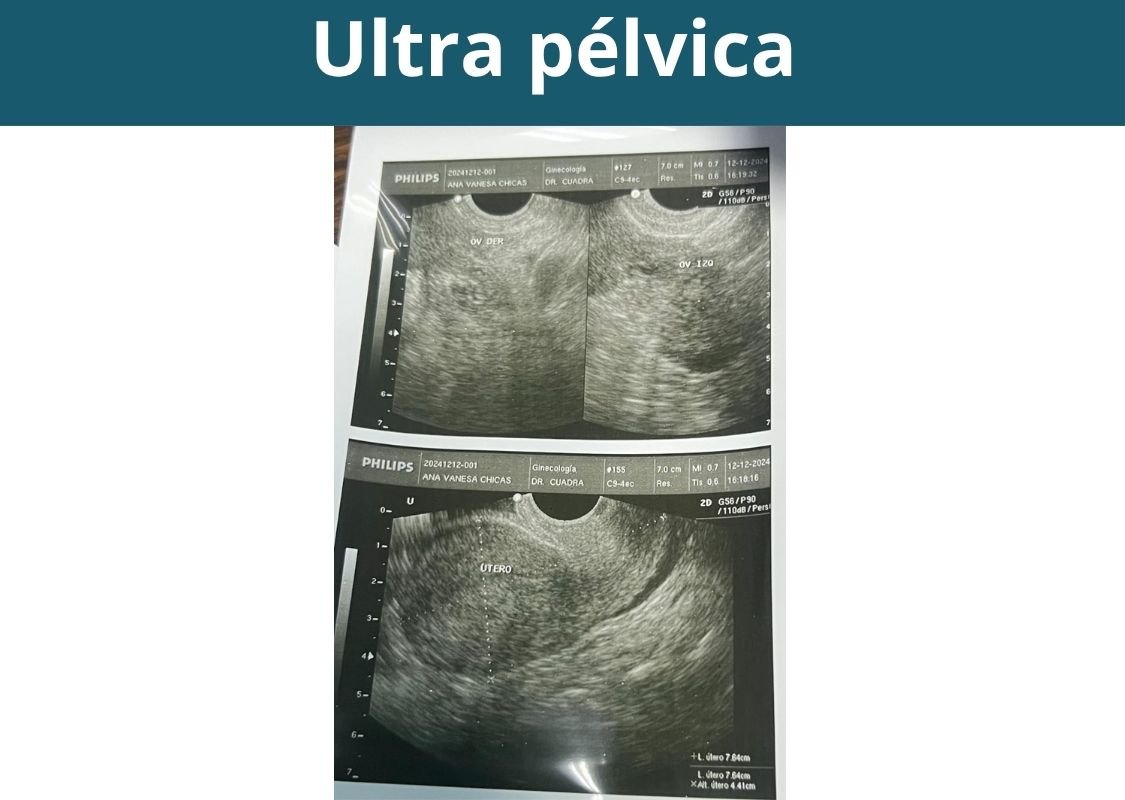

- Ultrasonografía pélvica abdominal (útero y ovarios).

- Ultrasonografía transvaginal (útero y ovarios).

Preparación de la paciente para ultrasonografías

- Para ultrasonografía vía abdominal: llevar vejiga llena.

- Para ultrasonografía vía vaginal: llevar vejiga vacía (orinar antes).

Otras ultrasonografías